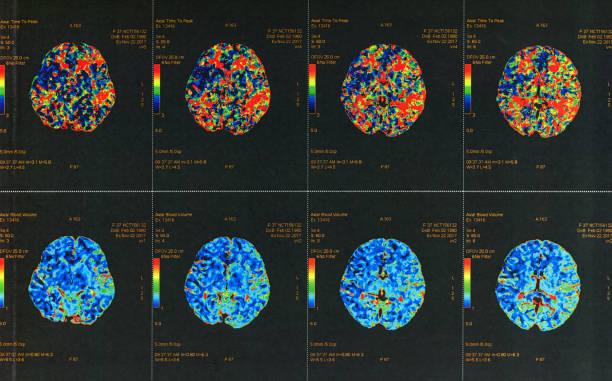

뇌출혈 전조증상 및 진단

뇌출혈이 발생하면 다양한 증상이 나타날 수 있습니다. 이러한 증상 중에서도 특히 편측 마비, 말 능력의 손실, 의식 변화 등이 나타날 경우 뇌출혈의 가능성을 고려해야 합니다. 이런 경우 즉시 의료기관을 찾아 진단 받아야 합니다.